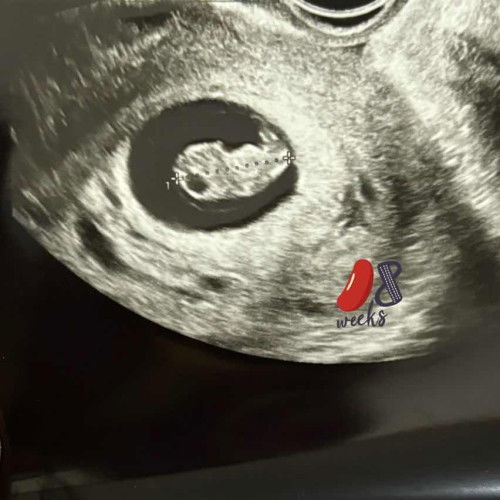

USG TVG 8week

Alhamdulillah setelah 2 minggu overthinking, akhirnya terlihat juga. Wktu periksa di usia 6week hanya terlihat kantung. Pas usg 8week udah ada bocilnya